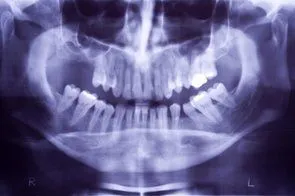

Loss of posterior teeth may result in excessive forces iStock_000002879017XSmall.jpg being placed on your remaining teeth. Fortunately, the use of dental implants and crowns allow you to replace these missing teeth. However, the position of the sinus in the upper posterior areas may be too low for proper placement of dental implants.

A simple procedure allows the sinus floor to be repositioned, creating enough space to properly place an implant. Various grafting materials are used to encourage your bone to grow more quickly into the area, helping to stabilize the dental implant. Replace with your own bone in this area the grafting material as it grows into the area.

Under certain conditions, an even simpler procedure can be utilized. When possible, the bone remaining under the sinus floor is gently “pushed up”, thus lifting the floor of the “dropped” sinus. Bone replacement materials are then placed beneath this lifted bone. Once again the bone materials are replaced as your body grow new bone into this area.

Sinus augmentation procedures are highly predictable, with studies reporting over 95% success. Following sufficient healing of a sinus augmentation (6-10 months), implants are placed in a predictable and successful manner. It is important to realize that if the sinus augmentation procedure does not result in enough bone for implant placement, additional bone may be regenerated through a second sinus augmentation procedure at the time of implant placement.